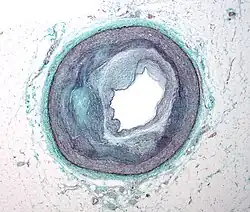

Typically, coronary artery disease occurs when part of the smooth, elastic lining inside a coronary artery (the arteries that supply blood to the heart muscle) develops atherosclerosis. With atherosclerosis, the artery's lining becomes hardened, stiffened, and accumulates deposits of calcium, fatty lipids, and abnormal inflammatory cells – to form a plaque. Calcium phosphate (hydroxyapatite) deposits in the muscular layer of the blood vessels appear to play a significant role in stiffening the arteries and inducing the early phase of coronary arteriosclerosis. This can be seen in a so-called metastatic mechanism of calciphylaxis as it occurs in chronic kidney disease and hemodialysis. Although these people have kidney dysfunction, almost fifty percent of them die due to coronary artery disease. Plaques can be thought of as large "pimples" that protrude into the channel of an artery, causing partial obstruction to blood flow. People with coronary artery disease might have just one or two plaques or might have dozens distributed throughout their coronary arteries. A more severe form is chronic total occlusion (CTO) when a coronary artery is completely obstructed for more than 3 months.[67]